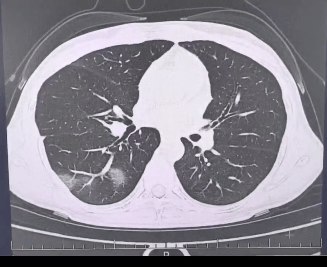

检查结果显示p币,

程女士的好几叶肺

都出现了“白肺”现象p币,

指间血氧饱和度只有 88%p币,

血心肌酶谱、肌钙蛋白的指标、肝功能的指标

也出现了明显的异常p币。

确诊流感(重型)p币!

图源:杭州市第三人民医院微信公众号